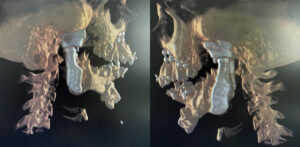

3D Printing in Healthcare has transformed the way industries like healthcare, automotive, manufacturing, and design operate. 3-D labs have revolutionised...

IntroductionCorrective jaw surgery, also known as Orthognathic surgery, changes the structure of your jawbone and brings your upper and lower...